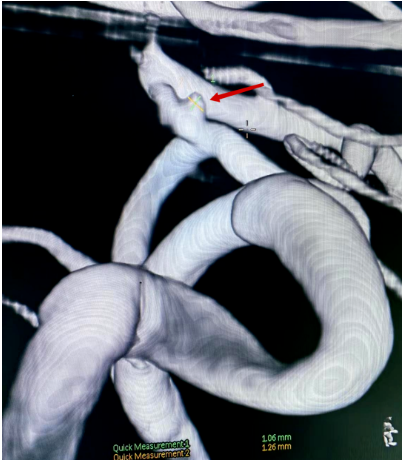

(图2 DSA血管3D成像)